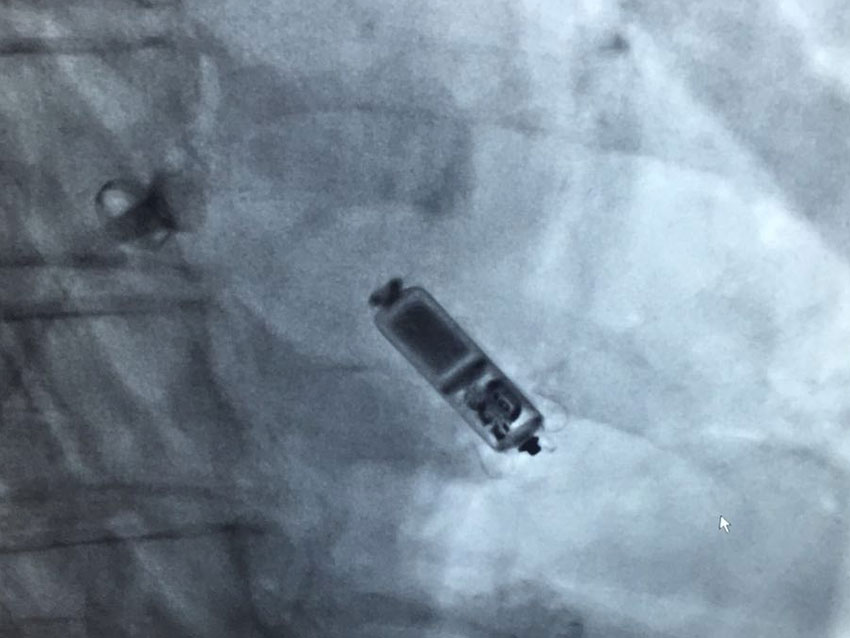

I’m deeply honored and humbled to receive the Interventional Cardiologist of the Year award at the Cardiac Excellence Awards 2025 . This recognition is a reflection not only of my journey but of the incredible support from almighty, my parents, my family, my loved ones, colleagues, mentors, and patients who inspire me every day.